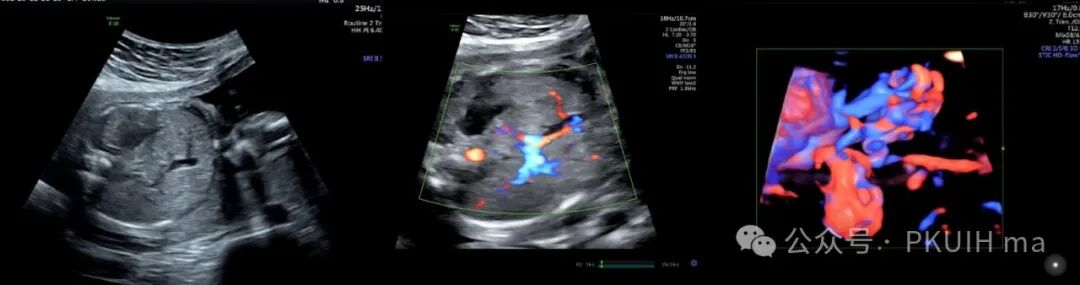

这是一例孕晚期发现的肝内占位最终病理为肝母细胞瘤